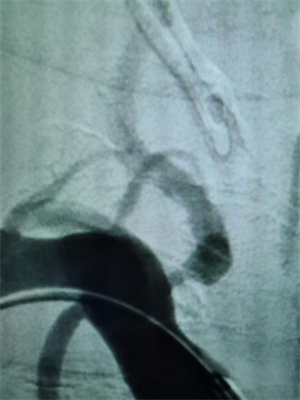

颅内动脉瘤破裂的“生死逆转战”

当天上午,64 岁的袁女士因突发剧烈头痛、呕吐急诊入院。CT显示蛛网膜下腔出血,进一步行头颈CTA检查确诊为颅内动脉瘤破裂。这是一种死亡率极高的疾病。神经内科介入团队在上级专家的指导下,迅速实施急诊栓塞手术,通过微导管将弹簧圈精准填入瘤体,成功栓塞破裂的动脉瘤。此类手术要求极高的精细度,术中需平衡栓塞效果与血管保护,我院团队的快速响应为患者赢得了生机。目前,袁女士神志清楚,病情稳定。

△图一:手术前可见后交通动脉瘤合并多个突起

△图二:手术后动脉瘤已经栓塞,造影不可见